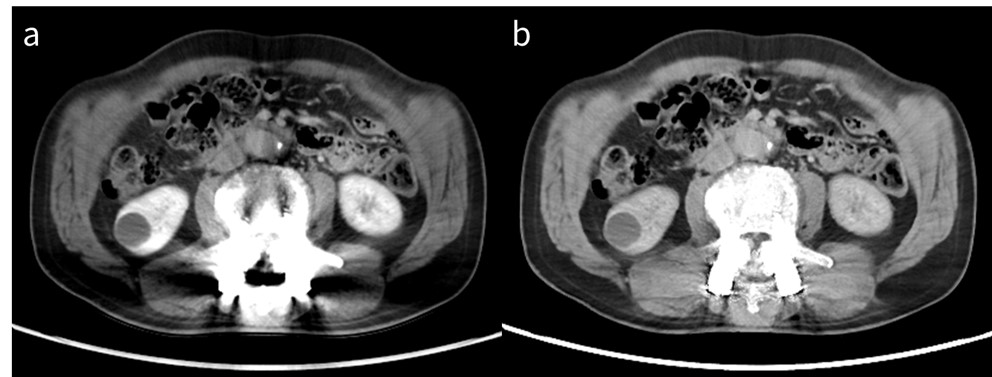

RevolutionApexElite_Gifu02_02.jpg

図1 膵癌の肝転移症例

a: 70 keV仮想単色X線画像

b: 40 keV仮想単色X線画像

40 keV仮想単色X線画像では、より肝転移巣と背景肝のコントラストが明瞭になっている。

これにより、低コントラスト病変の診断能向上にも一役買うことができ、日常診療では、診断能向上とまではいかなくとも、診断確信度を上げることのできる症例はそれなりの頻度で遭遇する(図2)。では、低keVの選択と言っても具体的に何keVを選択すればよいのだろうか。結論から言えば、何も考えずに最も低いエネルギーである40 keVの選択で構わない。40 keVを選択した場合、ノイズの上昇が気になるという声も聞こえてきそうだが、これもハードウェア・ソフトウェアの進歩によりノイズの気にならない、日常臨床で十分に使用できる画質感になっていると断言できる。